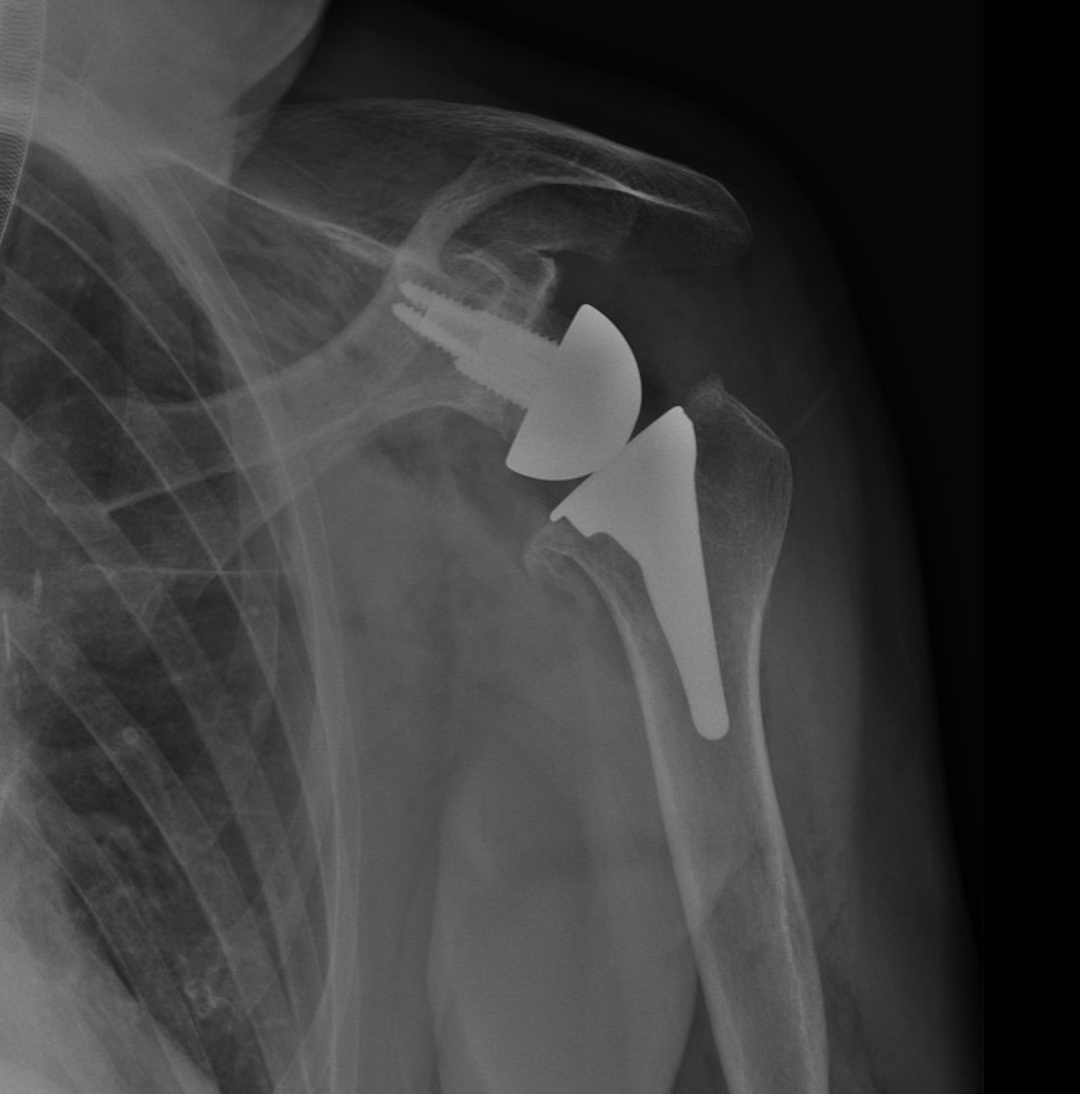

Unlike anatomic replacements, this technique reverses the normal ball-and-socket configuration: a metal ball is placed on the glenoid, and a socket is attached to the humerus.

This configuration allows the deltoid muscle, rather than the damaged rotator cuff, to power the shoulder, providing improved strength and stability.

X-ray image of a shoulder with a shoulder replacement implant, including a metal humeral stem and a cup in the shoulder socket.